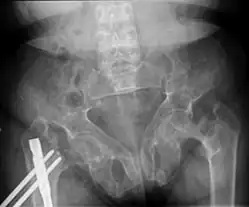

Renal osteodystrophy is usually diagnosed after treatment for end-stage kidney disease begins; however the CKD-MBD starts early in the course of CKD.[1][6] In advanced stages, blood tests will indicate decreased calcium and calcitriol (vitamin D) and increased phosphate, and parathyroid hormone levels. In earlier stages, serum calcium, phosphate levels are normal at the expense of high parathyroid hormone and fibroblast growth factor-23 levels. X-rays will also show bone features of renal osteodystrophy (subperiostic bone resorption, chondrocalcinosis at the knees and pubic symphysis, osteopenia and bone fractures) but may be difficult to differentiate from other conditions. Since the diagnosis of these bone abnormalities cannot be obtained correctly by clinical, biochemical, and imaging methods (including measurement of bone-mineral density), bone biopsy has been, and still remains, the gold standard analysis for assessing the exact type of renal osteodystrophy.[6][16]